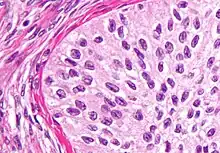

| High magnification micrograph of a Brenner tumor, a type of surface epithelial-stromal tumor. H&E stain. | |

Brenner tumor

Brenner tumors are uncommon surface-epithelial stromal cell tumors in which the epithelial cell (which defines these tumors) is a transitional cell. These are similar in appearance to bladder epithelia. The tumors may be very small to very large, and may be solid or cystic. Histologically, the tumor consists of nests of the aforementioned transitional cells within surrounding tissue that resembles normal ovary. Brenner tumors may be benign or malignant, depending on whether the tumor cells invade the surrounding tissue.